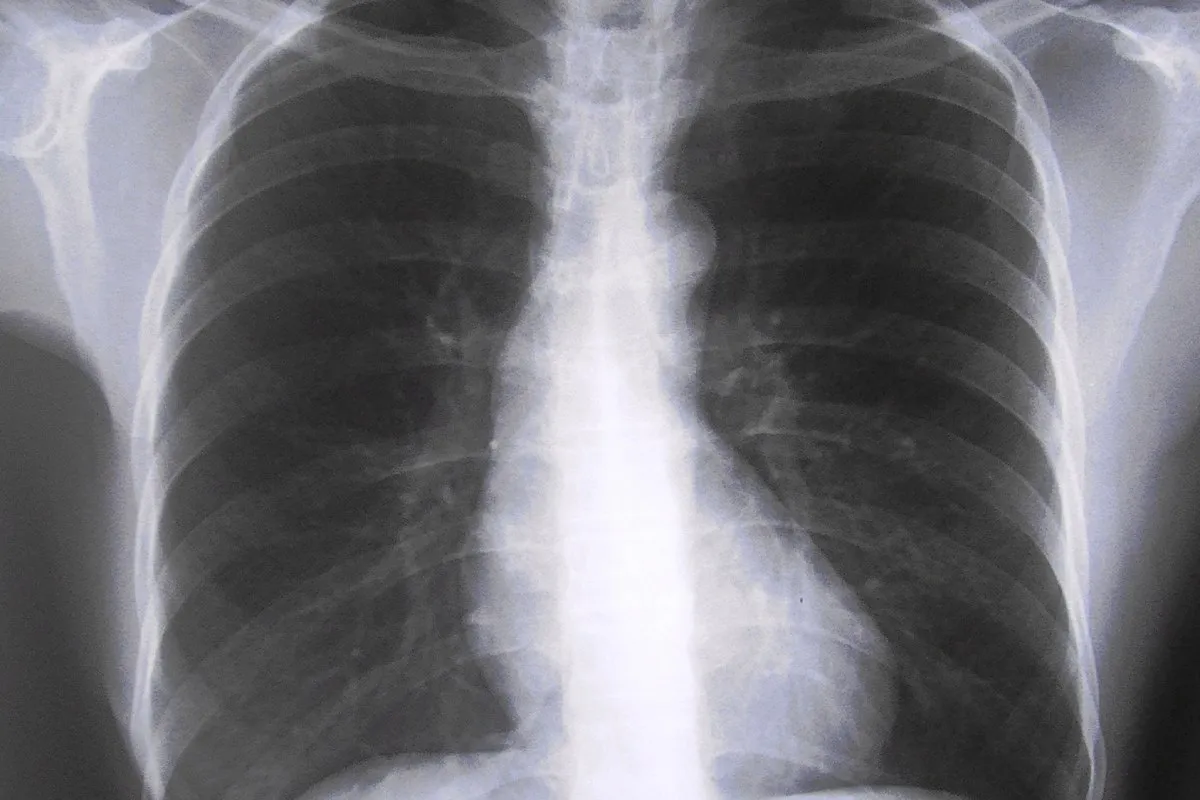

Genética y factores de riesgo inciden en fibrosis pulmonar idiopática

De las características del envejecimiento, dos tienen relación con la FPI: acortamiento exagerado de los telómeros (repeticiones de nucleótidos localizados al final de los cromosomas) en las células epiteliales, y la senescencia epitelial acelerada.